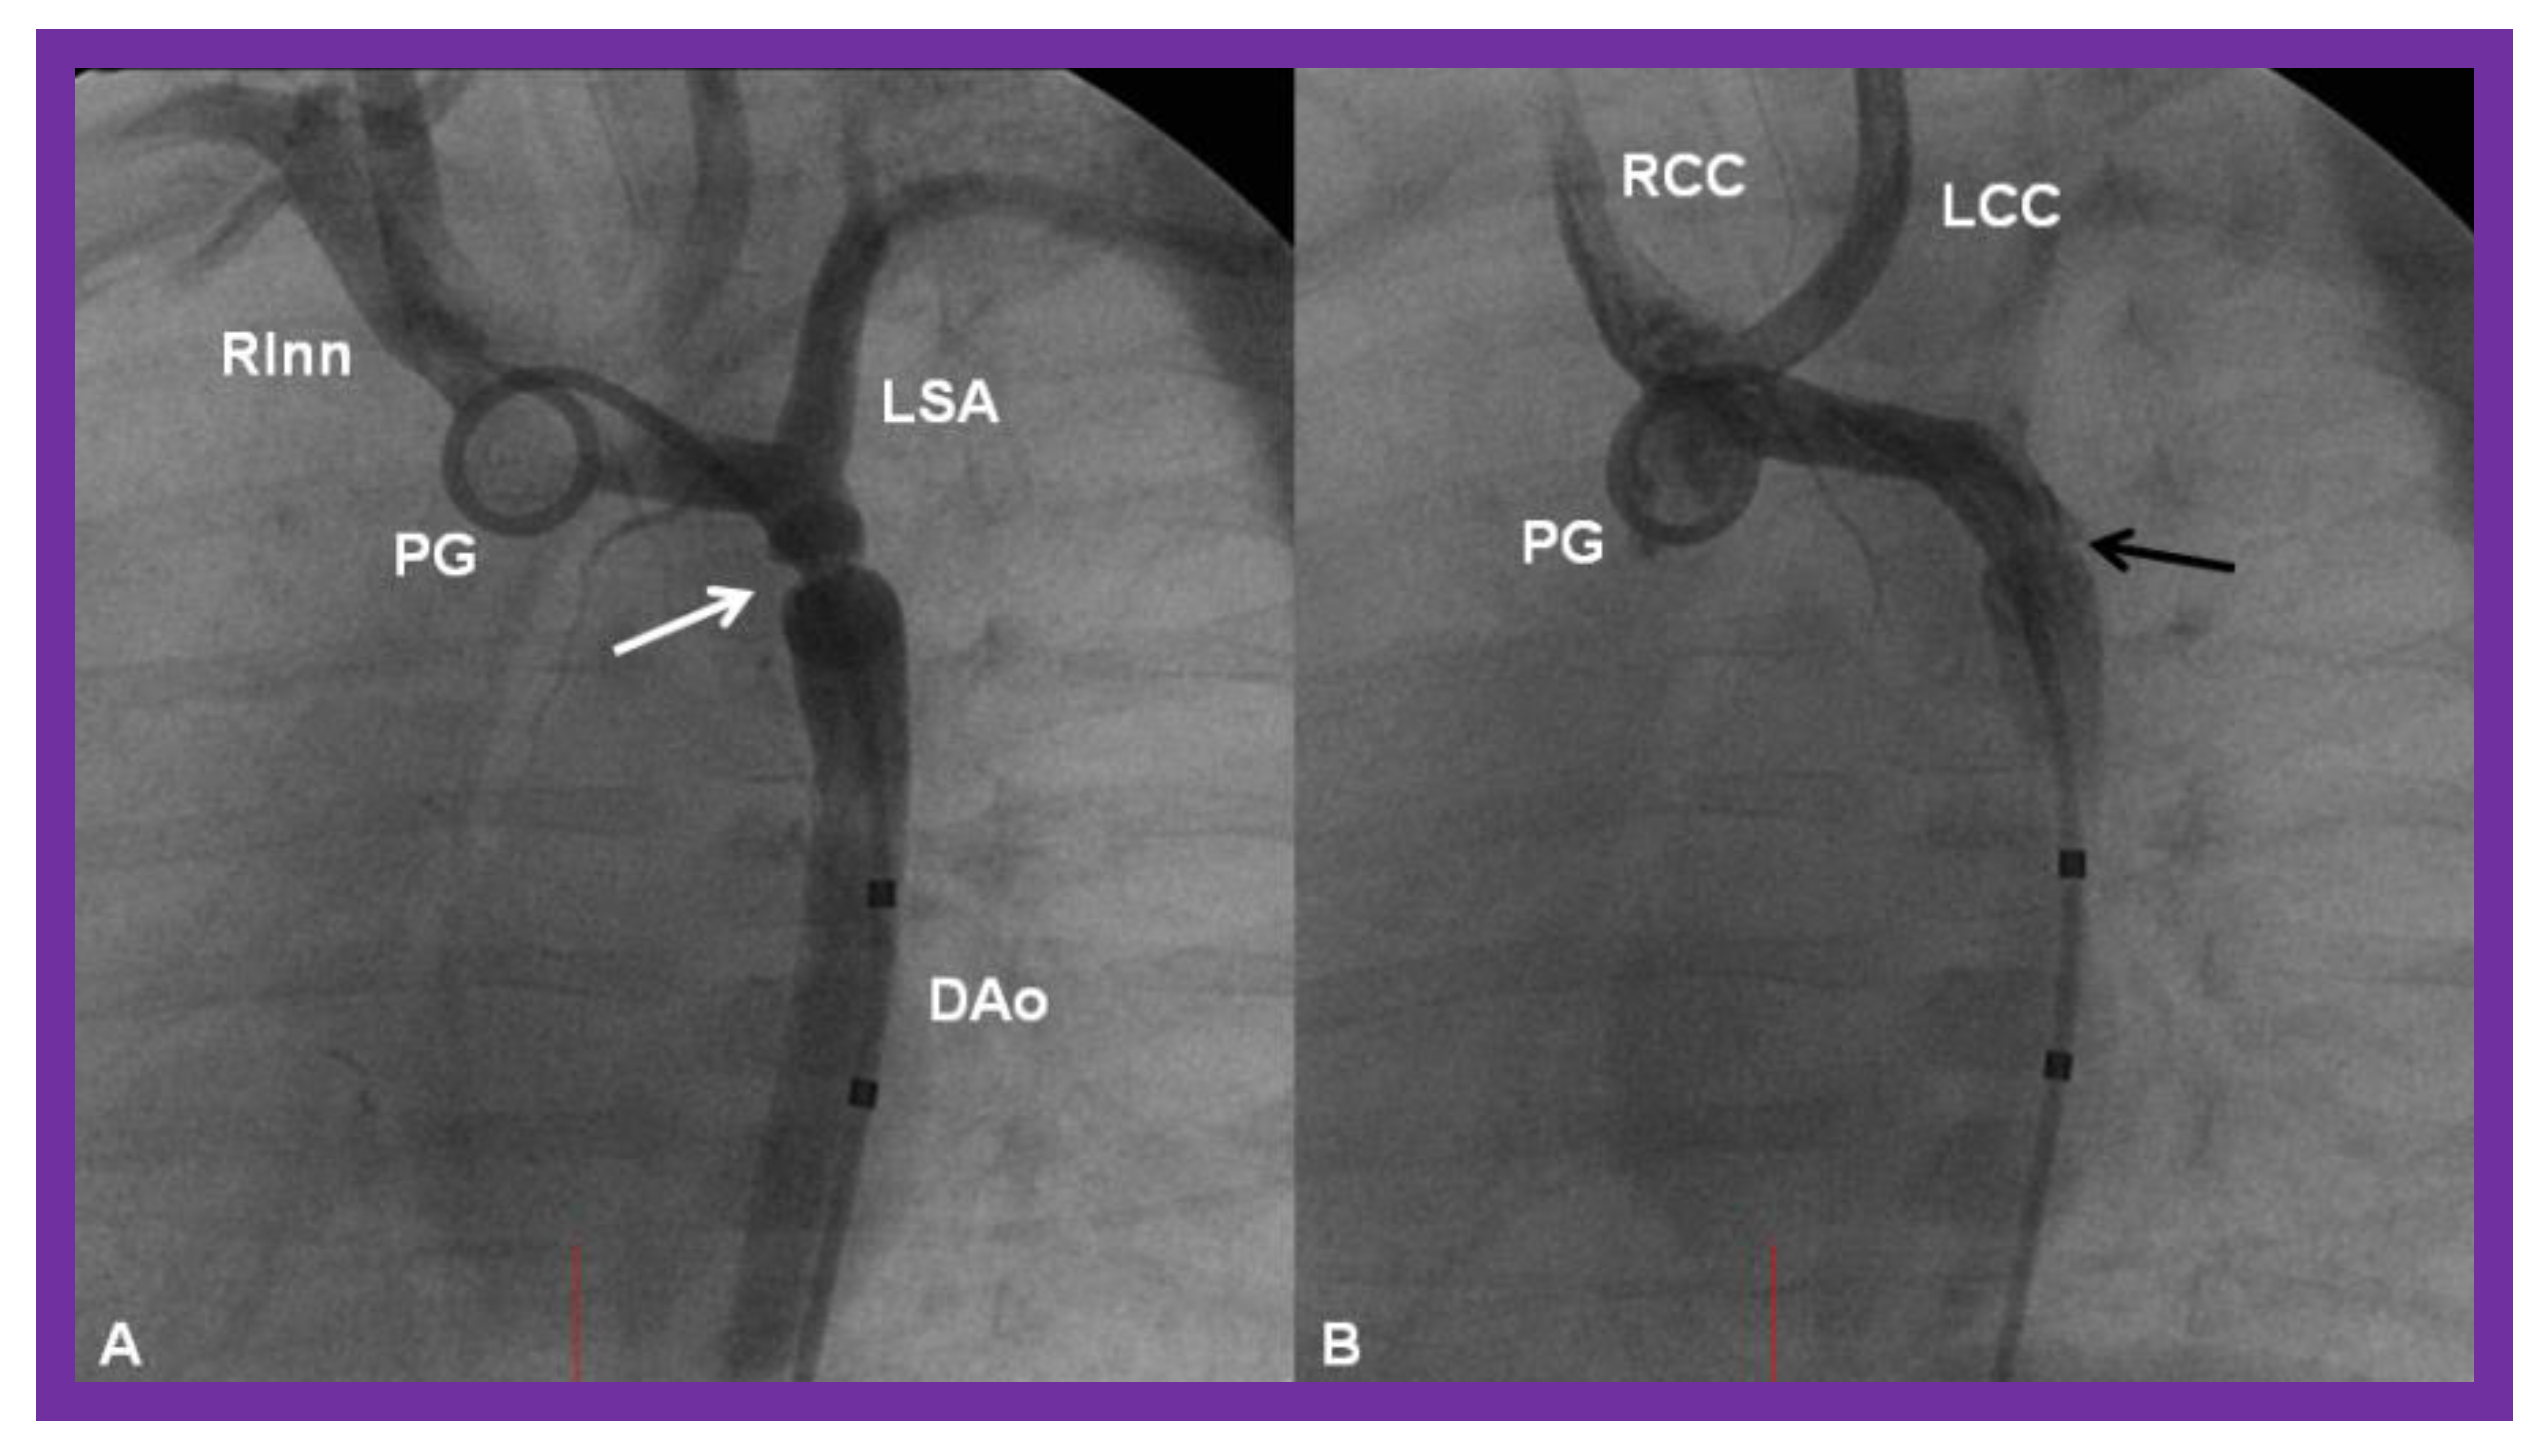

- Rao, P.S.; Balfour, I.C.; Singh, G.K.; Jureidini, S.B.; Chen, S. Bridge stents in the management of obstructive vascular lesions in children. Am. J. Cardiol. 2001, 88, 699–702. [Google Scholar] [CrossRef]

- Rao, P.S. Stents in the management of congenital heart disease in the pediatric and adult patients. Indian Heart J. 2001, 53, 714–730. [Google Scholar] [PubMed]

- Sahu, R.; Rao, P.S. Transcatheter stent therapy in children: An update. Pediatrics Ther. 2012, S5. [Google Scholar] [CrossRef]

- Rao, P.S. Stents in the Management of Vascular Obstructive Lesions Associated with Congenital Heart Disease. In Cardiac Catheterization and Imaging (From Pediatrics to Geriatrics); Vijayalakshmi, I.B., Ed.; Jaypee Publications: New Delhi, India, 2015; pp. 573–598. [Google Scholar]

- Rao, P.S. Stents. In Pediatric Cardiology: How It Has Evolved Over The Last 50 Years; Rao, P.S., Ed.; Cambridge Scholars Publishing: New Castle upon Tyne, UK, 2020; pp. 511–559. ISBN 9781527548886. [Google Scholar]